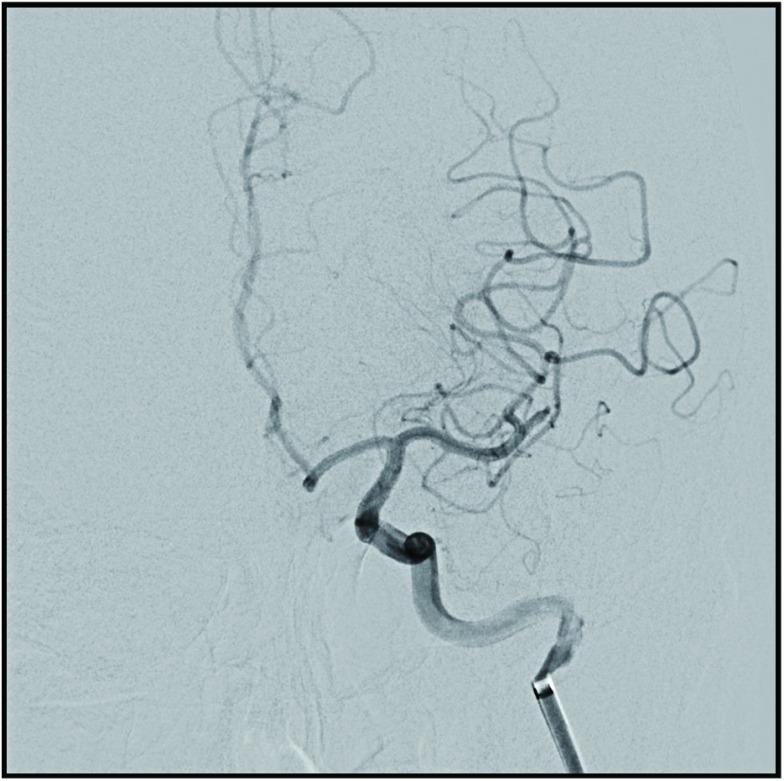

An 82-year-old female who had undergone a mitral valve annuloplasty developed sudden aphasia, right hemiplegia, and right unilateral spatial neglect on postoperative day 10. Cranial MRI indicated occlusion of the horizontal segment of the left middle cerebral artery. During mechanical thrombectomy, a vasospasm snagged the stent, and re-sheathing attempts failed repeatedly. We wedged the microcatheter into the spasm site and slowly injected a solution containing 1 cc of nicardipine, 2 cc of contrast medium, and 2 cc of heparin in normal saline intra-arterially. After several minutes, we retracted the Trevo wire slightly and easily removed the stent. The thrombus adhered to the retrieved stent. Post-retrieval imaging showed that the branch was completely recanalized.

一名82岁女性,曾接受二尖瓣环成形术,术后第10天突然出现失语、右侧偏瘫和右侧单侧空间忽视。头颅MRI显示左侧大脑中动脉水平段闭塞。在机械取栓过程中,血管痉挛卡住了支架,多次尝试重新收回支架均失败。我们将微导管楔入痉挛部位,并经动脉缓慢注射一种溶液,该溶液包含1毫升尼卡地平、2毫升造影剂和2毫升肝素溶于生理盐水中。几分钟后,我们稍微回撤Trevo导丝并轻松取出了支架。血栓附着在回收的支架上。取栓后成像显示分支完全再通。